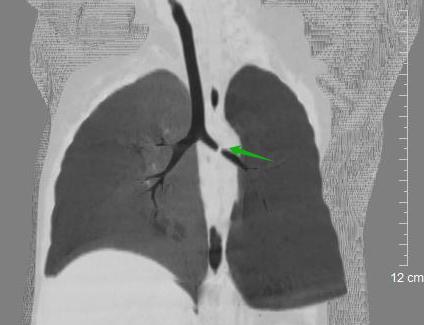

小曦,男,9岁,上体育课时突然龋齿脱落,随后出现呛咳,辗转多家医疗机构治疗3周,咳嗽无缓解,完善胸部CT检查发现右主支气管异物伴右侧阻塞性肺气肿,遂入院行“支气管镜气管异物取出术”,术中取出一颗龋齿,随后呼吸道症状缓解。

(绿色箭头为异物)